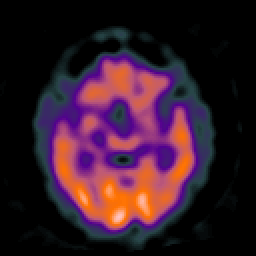

Huntington's Chorea, MR -- Slice #8

[Home][Help][Clinical] Slice 8